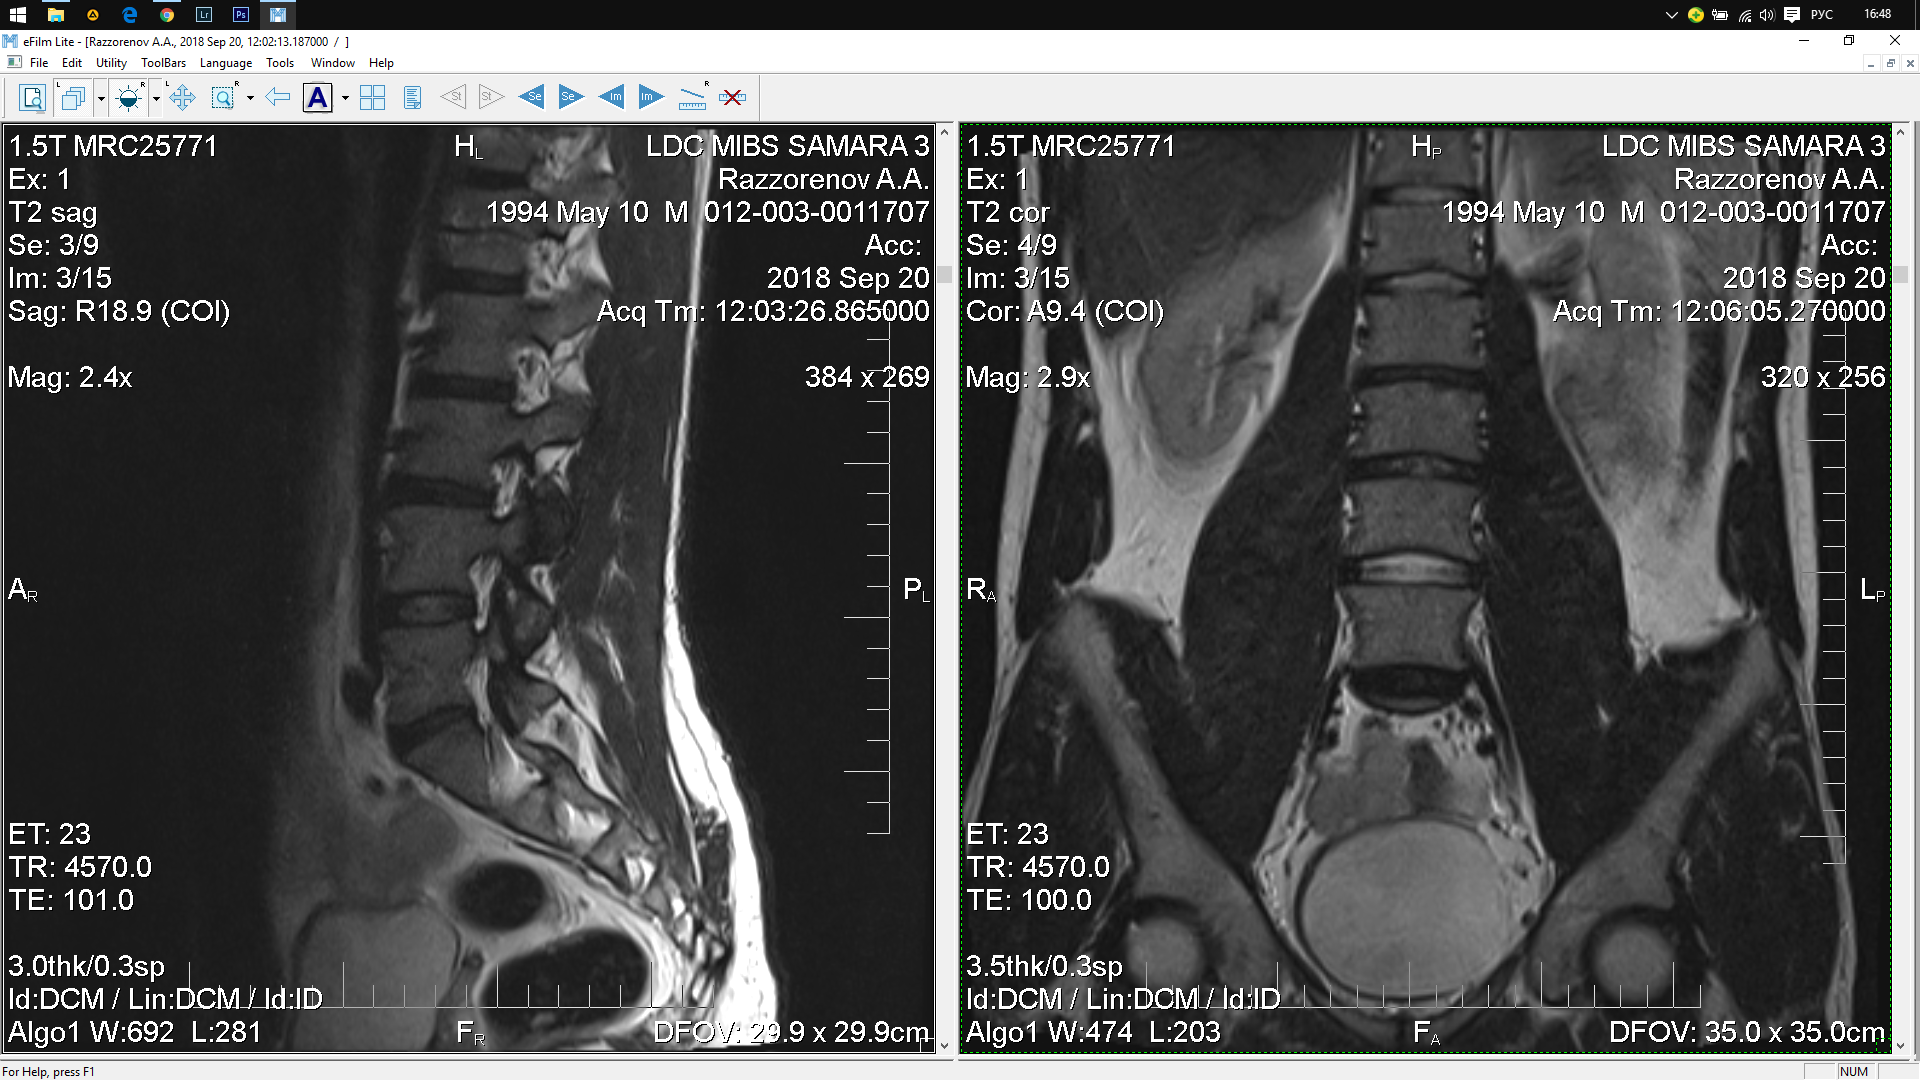

Тренировки с межпозвоночной грыжей.